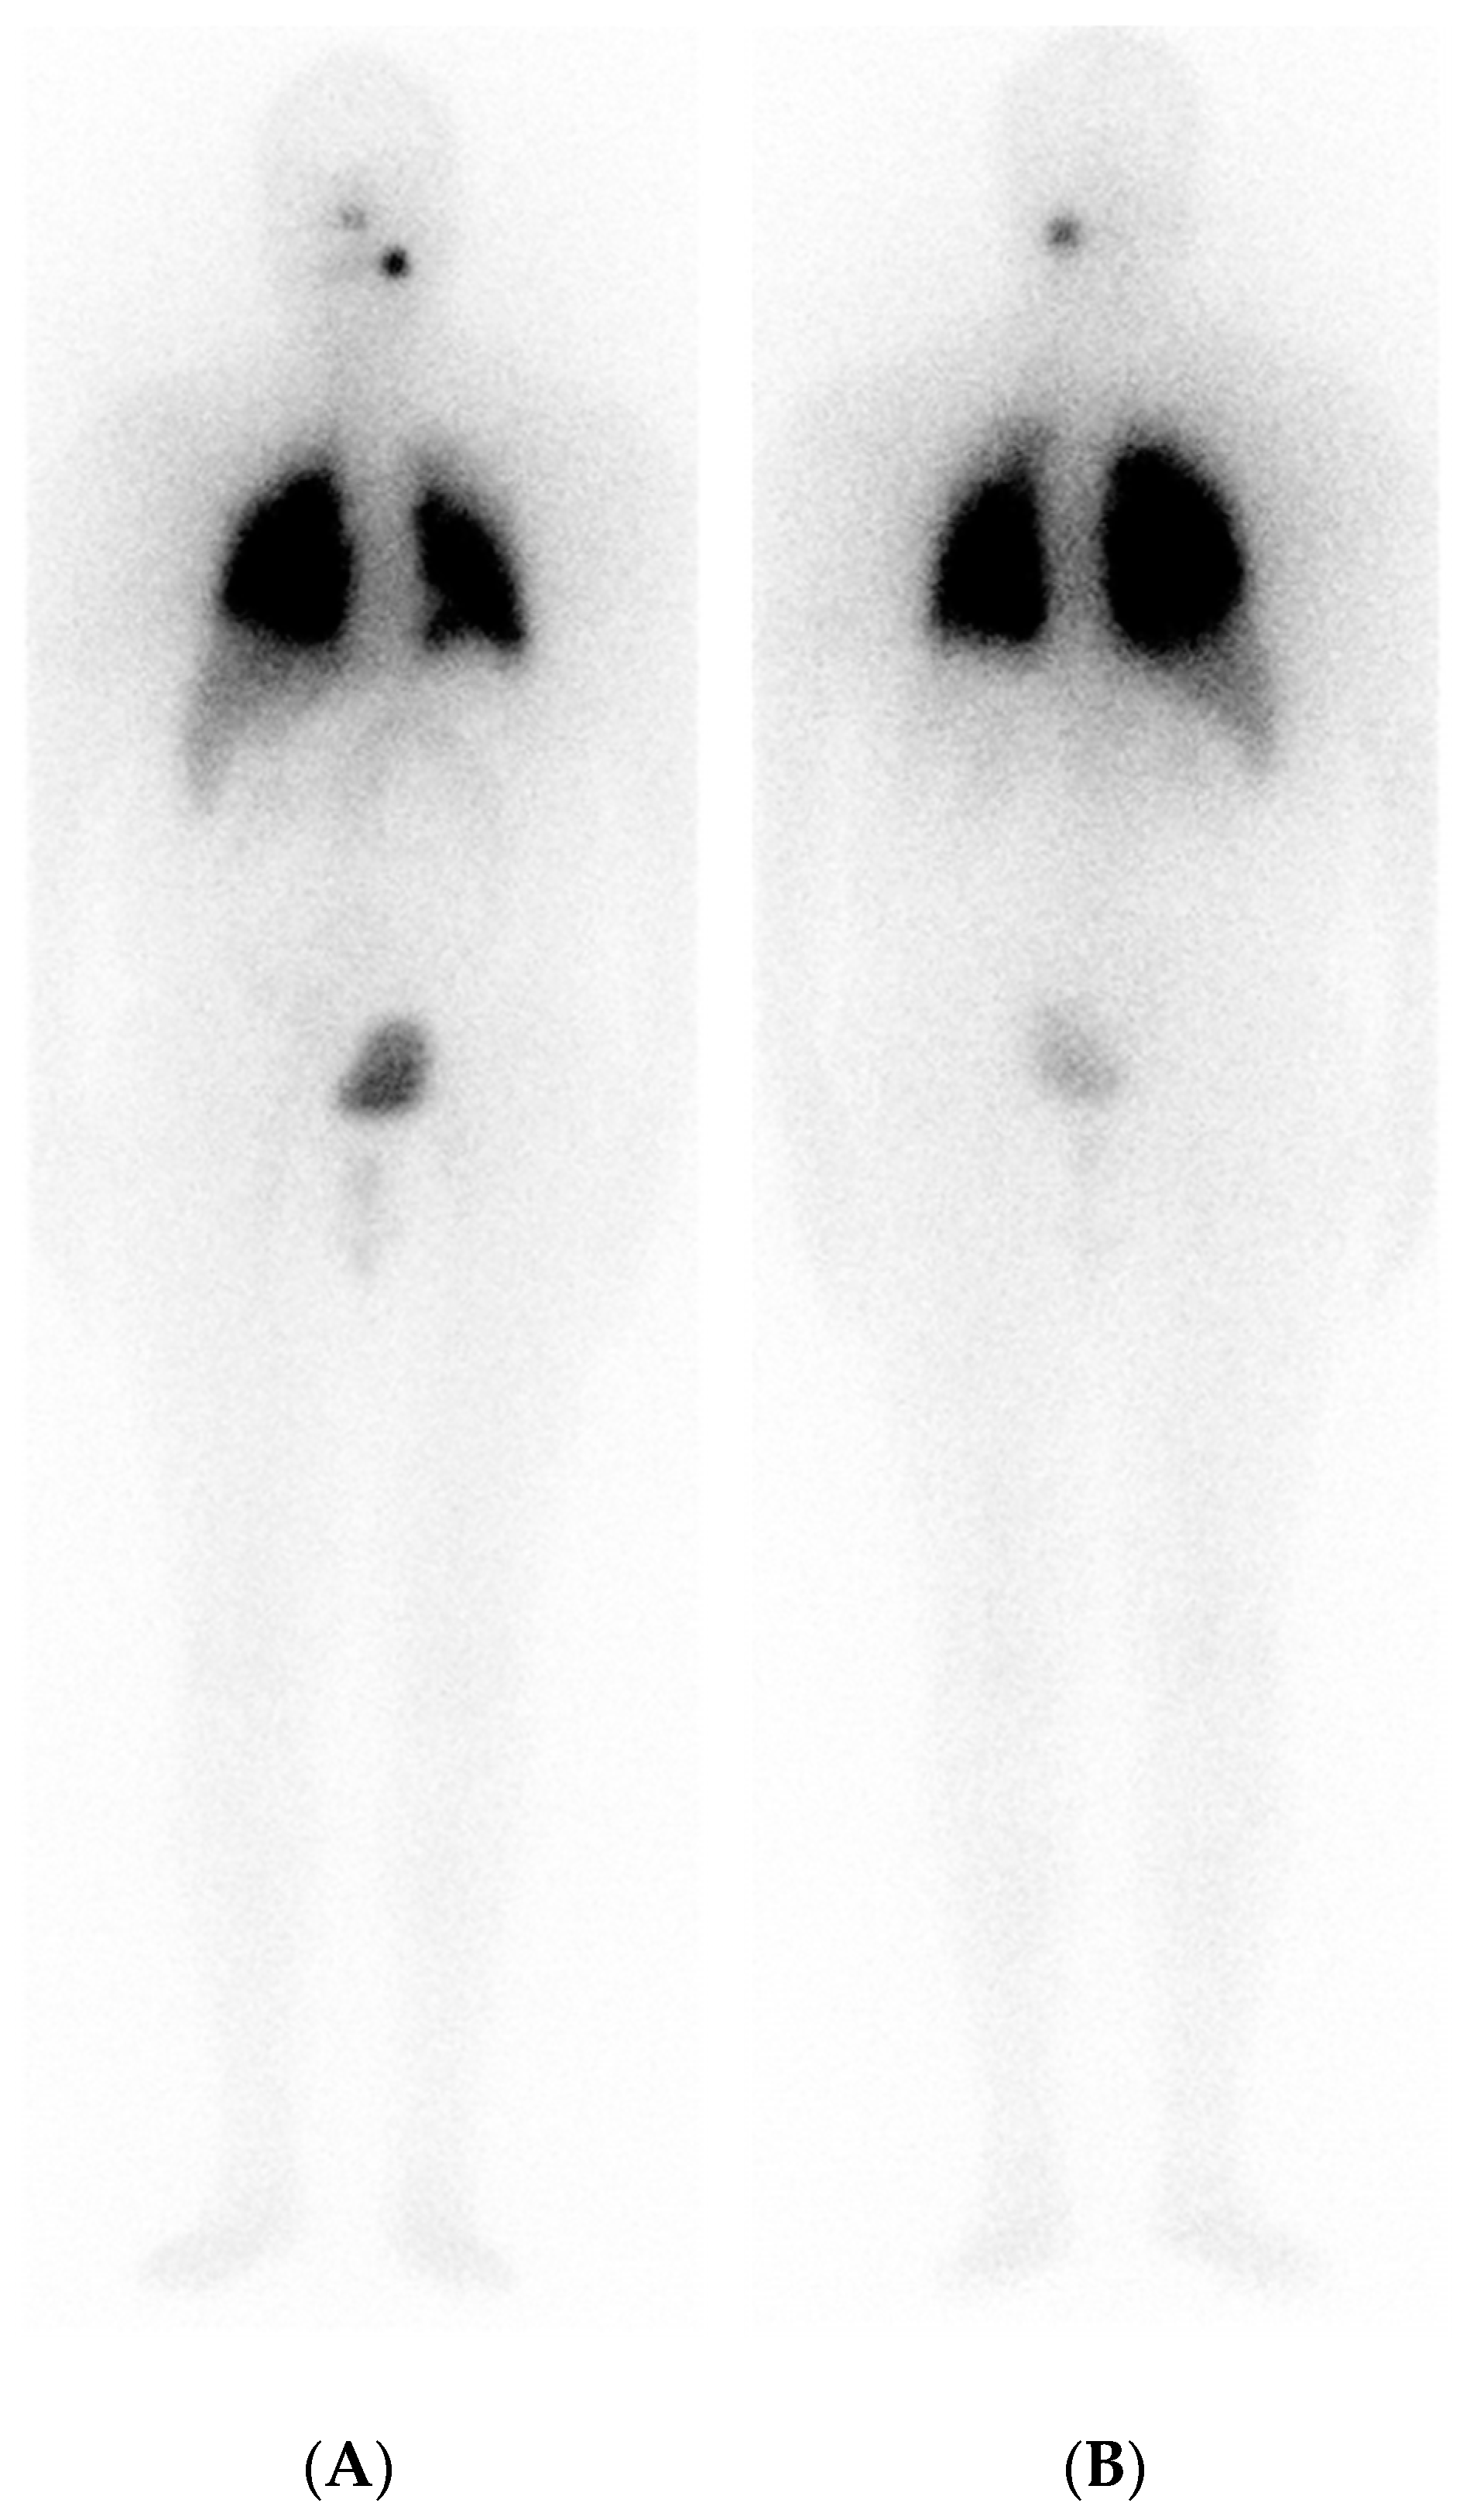

6. A Case of Re-Differentiation

|